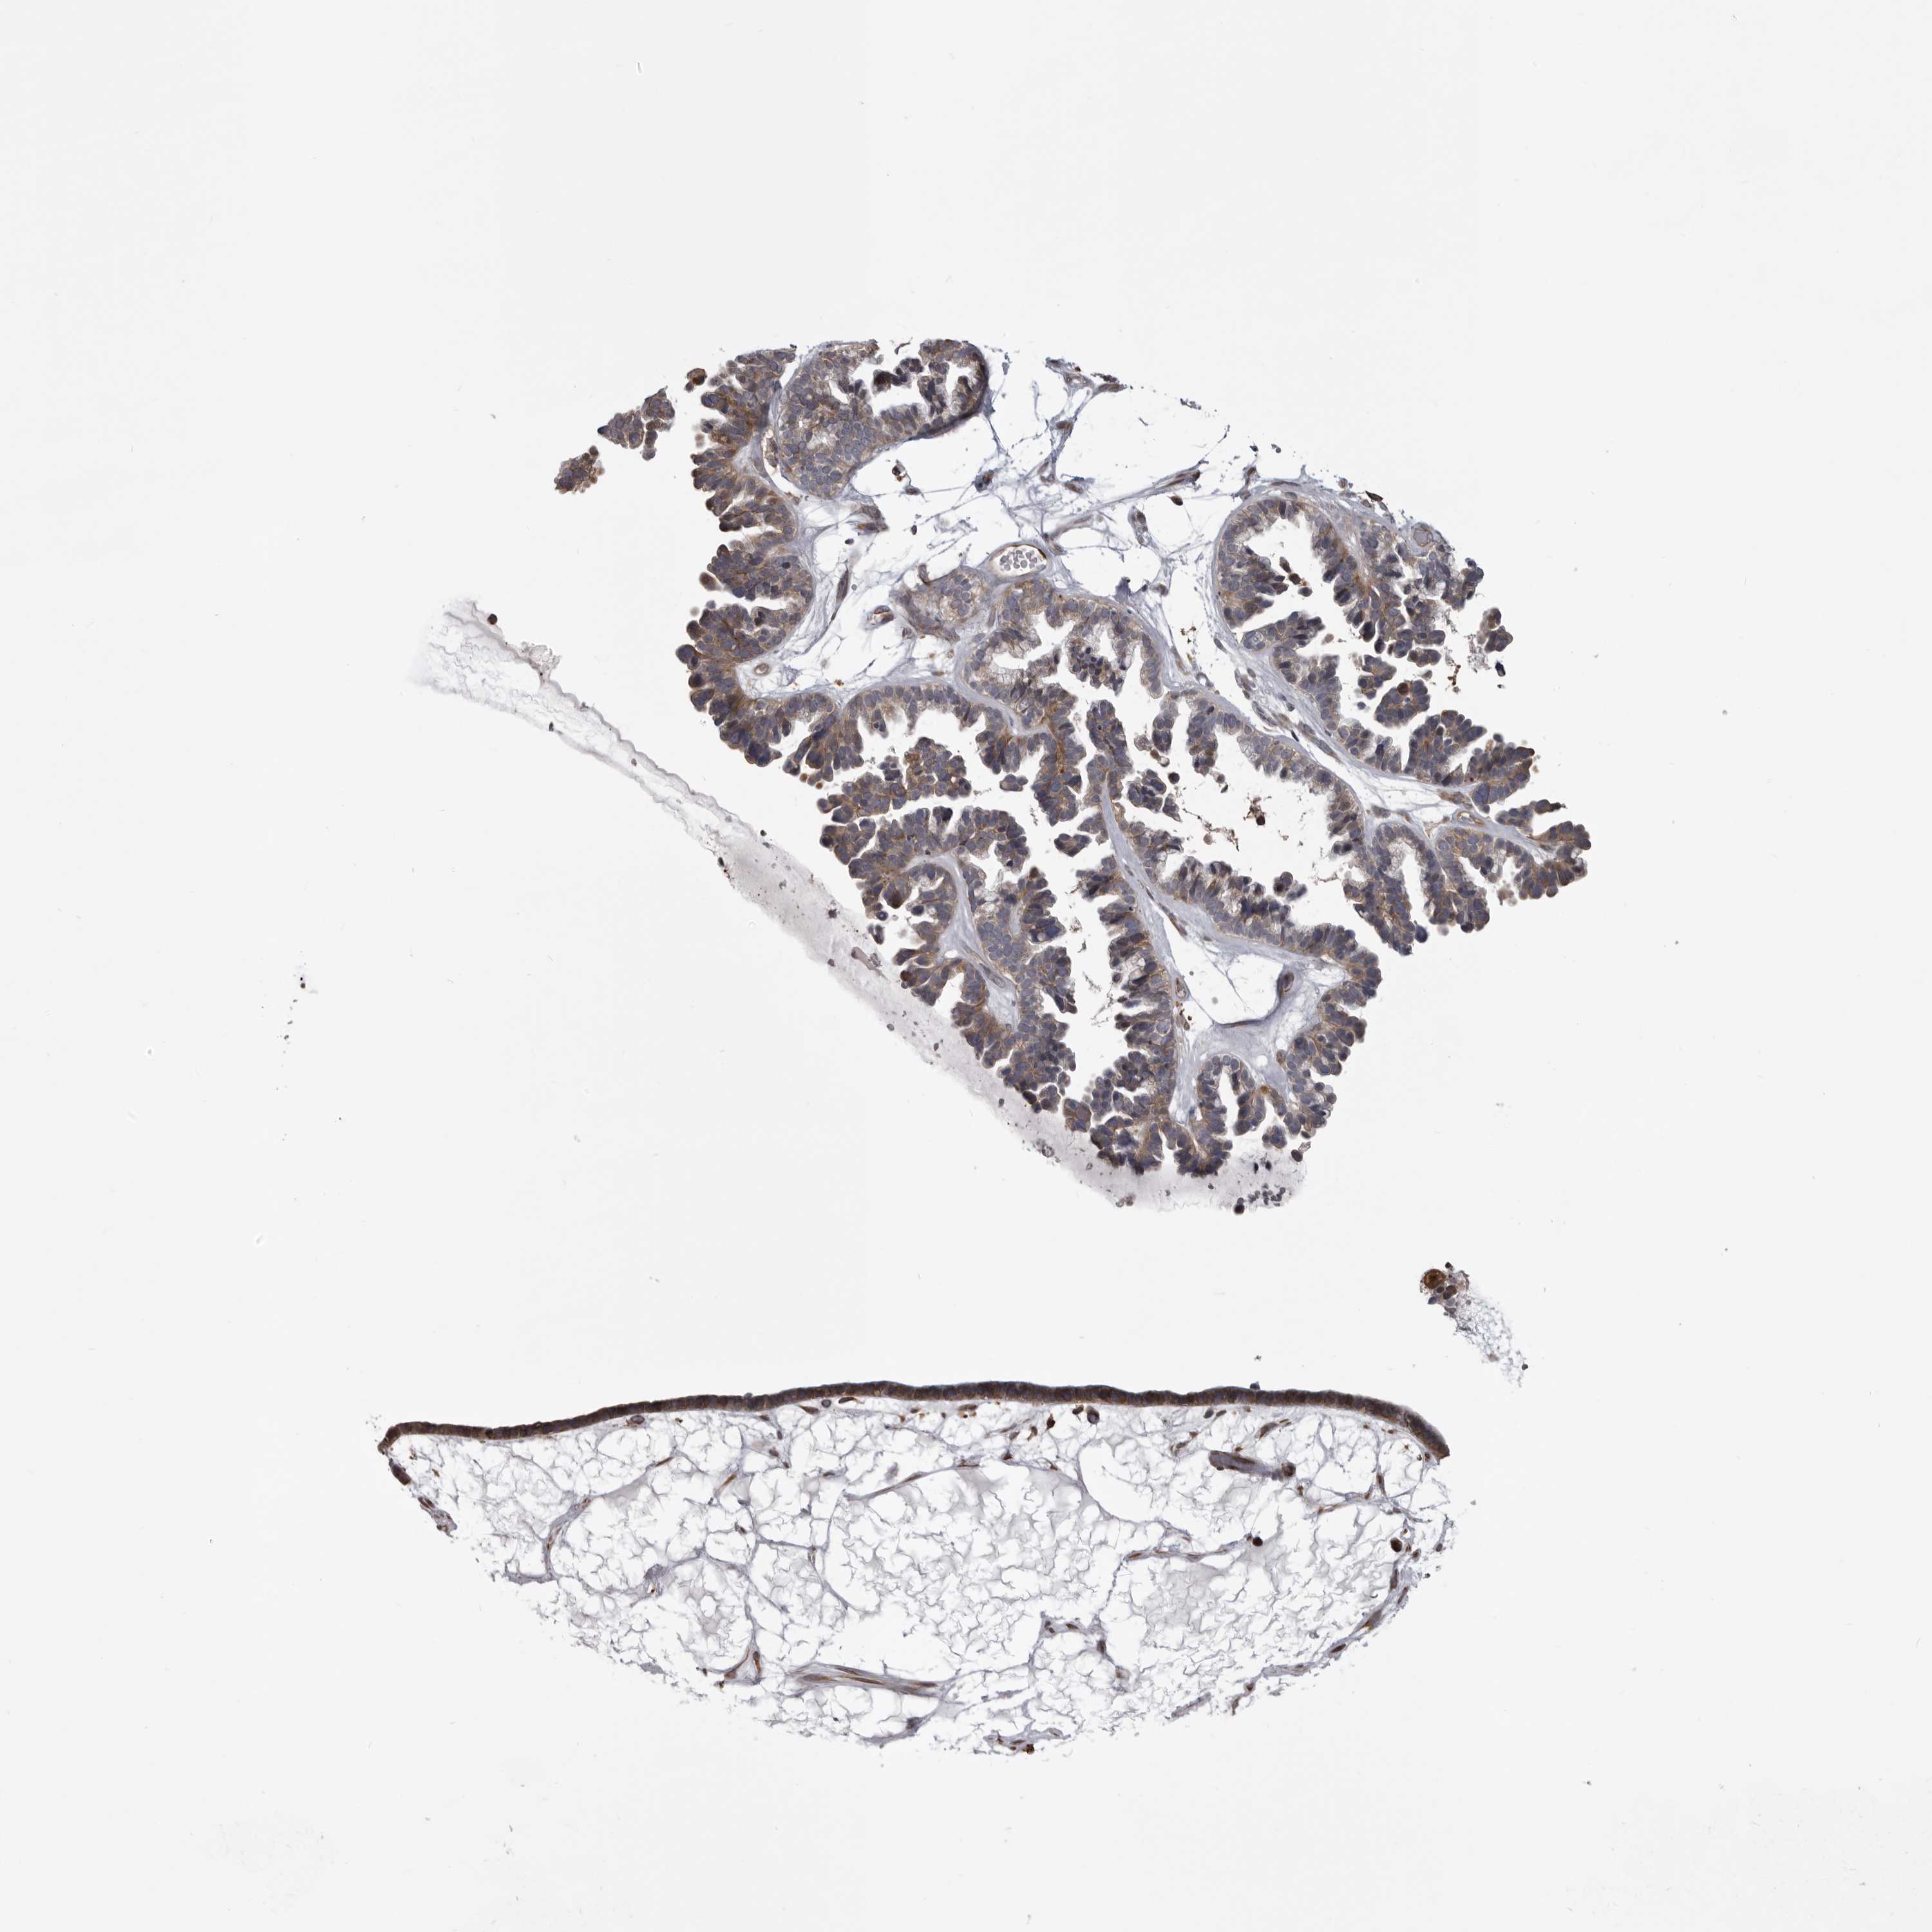

OVARIAN CANCER - Protein expressioni

A mouse-over function shows sample information and annotation data. Click on an image to view it in a full screen mode. Samples can be filtered based on level of antibody staining by selecting one or several of the following categories: high, medium, low and not detected. The assay and annotation is described here.

Note that samples used for immunohistochemistry by the Human Protein Atlas do not correspond to samples in the TCGA dataset.

Antibody stainingi

Antibody staining in the annotated cell types in the current human tissue is reported as not detected, low, medium, or high, based on conventional immunohistochemistry profiling in selected tissues. This score is based on the combination of the staining intensity and fraction of stained cells.

Each image is clickable and will lead to virtual microscopy that enables deeper exploration of all samples and also displays staining intensity scores, fraction scores and subcellular localization as well as patient and tissue information for each sample.

Antibody HPA027470

Staining

High

Medium

Low

Not detected

Intensity

Strong

Moderate

Weak

Negative

Quantity

>75%

75%-25%

<25%

None

Location

Nuclear

Cytoplasmic/membranous

Cytoplasmic/membranous,nuclear

Cystadenocarcinoma, serous, NOS

Carcinoma, endometroid

Cystadenocarcinoma, mucinous, NOS

Carcinoma, NOS